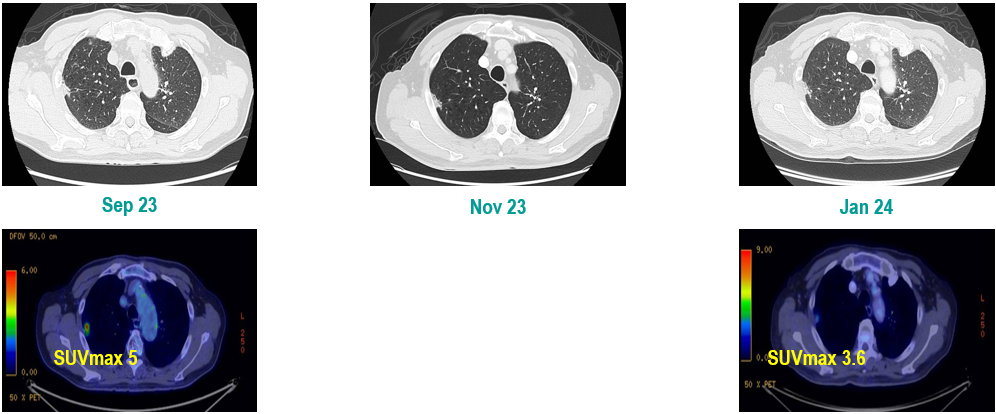

PET-CT(2023年9月):右下肺叶发现6.9×6.7×6.6cm的FDG高摄取肿块,伴右侧第7、8肋骨侵犯可疑,右肺门淋巴结肿大,双肺上叶多发结节,考虑腺癌谱系疾病。

CT及PET-CT随访(2023年11月、2024年1月):评估新辅助治疗效果,右下肺叶肿块缩小,右肺门淋巴结代谢活性消失,右肺上叶结节稳定但代谢活性降低,左肺上叶及双侧磨玻璃样病变稳定。

新辅助治疗:患者接受4周期新辅助化疗联合免疫治疗(培美曲塞、顺铂、纳武利尤单抗),治疗后影像学显示肿块缩小,代谢活性降低。